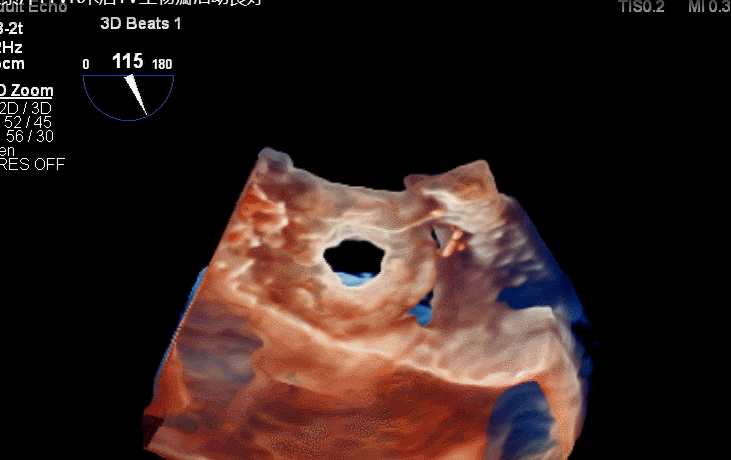

术后三维超声同时显示MV机械瓣及新的TV生物瓣